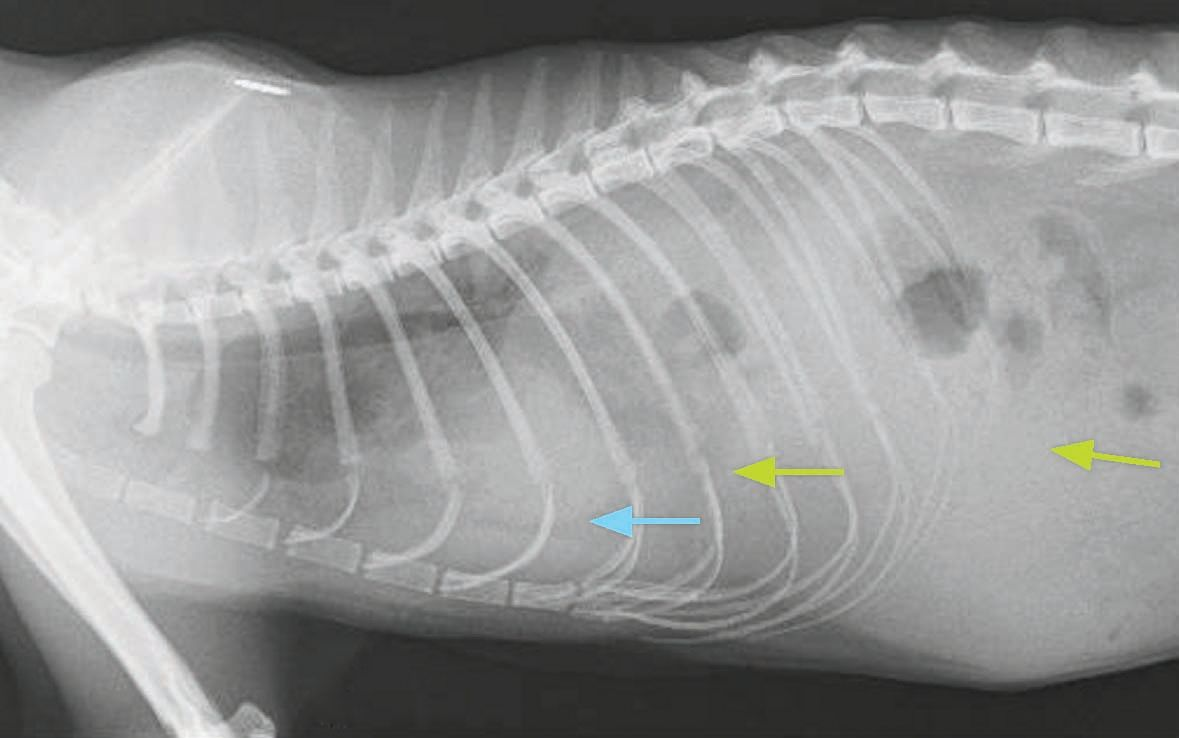

Cat X Ray. Diaphragmatic Hernia in Cat. Stock Image Image of anatomy Can A Cat Live With A Diaphragmatic Hernia a diaphragmatic hernia is a condition in which a break in the diaphragm allows protrusion of abdominal organs into the chest. learn about the causes, pathophysiology and diagnosis of traumatic diaphragmatic hernia (tdh) in cats, a. Diaphragmatic hernias occur when an abdominal organ (such as the stomach, liver,. learn about the causes, signs, diagnosis, and treatment of. Can A Cat Live With A Diaphragmatic Hernia.

X Ray Diaphragmatic Hernia Cat Side Stock Photo 1253071330 Shutterstock Can A Cat Live With A Diaphragmatic Hernia a diaphragmatic hernia is a condition in which a break in the diaphragm allows protrusion of abdominal organs into the chest. A hernia occurs when there's an abnormal hole in the muscle wall of the abdomen or diaphragm. diaphragmatic hernia in cats. cases of diaphragmatic hernia may be either congenital (from birth) or from trauma (not always. Can A Cat Live With A Diaphragmatic Hernia.